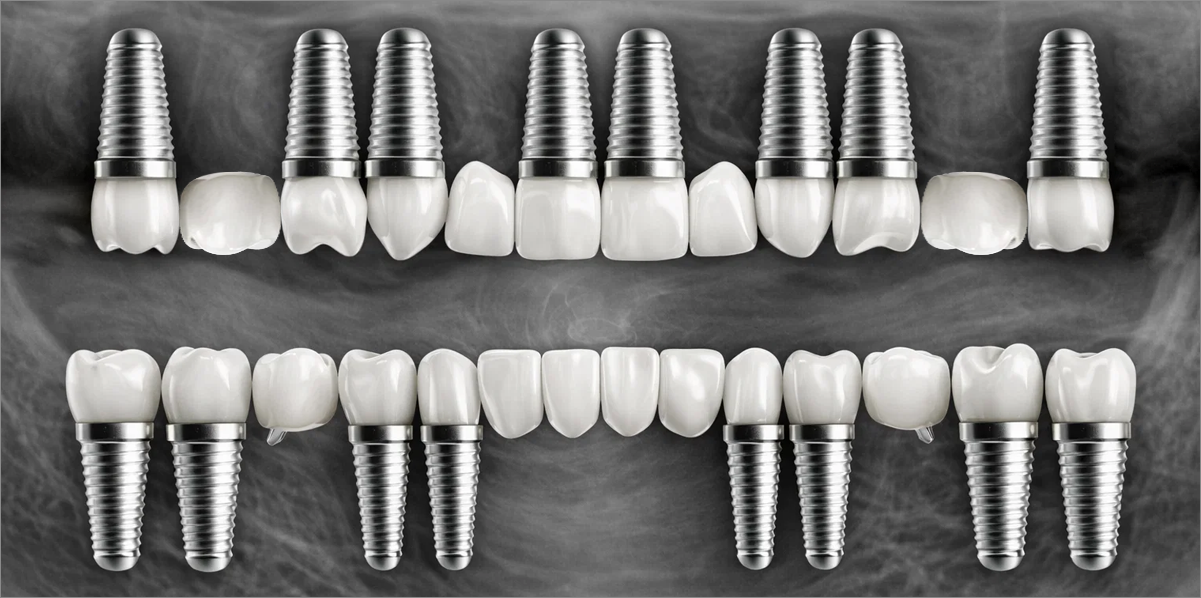

전체 임플란트

위 아래 치아가 정확하게 맞아야하는 고난이도 임플란트

임상 경험이 많은 숙련된 전문의의 섬세한 기술력이 중요합니다.